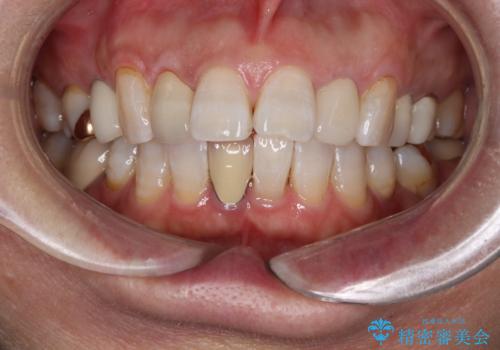

数年ぶりに歯のクリーニング(PMTC)

- しばらく歯科へ行っていなかったため綺麗にクリーニングしたいとのことでした。全体的に汚れが付着していたためPMTC60分コースを行いました。